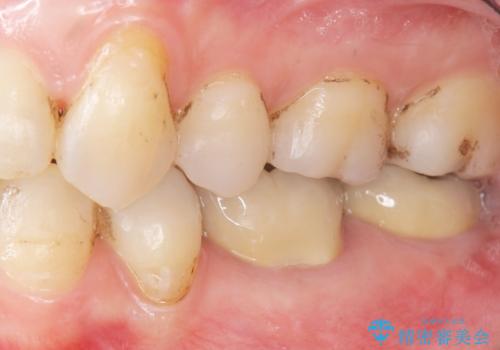

低予算で銀歯を白くしたい 50代女性

- 低予算で銀歯を白くしたいとご希望し来院された患者様です。

右上小臼歯(右上5)はオールセラミッククラウン(e-max press)、下顎臼歯(下顎両側67)はメタルボンドクラウンによりやりかえることにしました。

銀歯がなくなったとことで口元の印象が明るくなり、ご満足頂けました。

「これで大きく口を開けて笑っても大丈夫だわ!」と喜んで下さいました。

~クラウンの種類~

右上小臼歯(右上5):オールセラミッククラウン エコノミー

下顎両側臼歯(下顎両側67):メタルボンドクラウン エコノミー